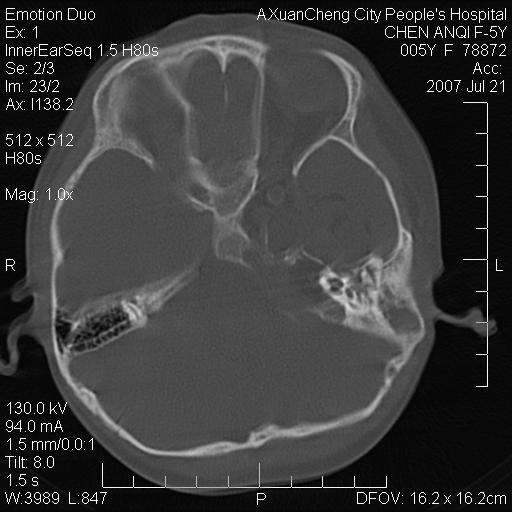

标题: PED0273:5岁,左耳流脓痛疼一周,颅底骨质破坏 [打印本页]

标题: PED0273:5岁,左耳流脓痛疼一周,颅底骨质破坏

患儿5岁,左耳流脓痛疼一周,左外耳道肉芽组织填塞 软组织窗显示病灶内结节状低密度影为气体密度

左侧中耳炎并胆脂瘤,左颞骨岩部骨质破坏并颅内感染积气。